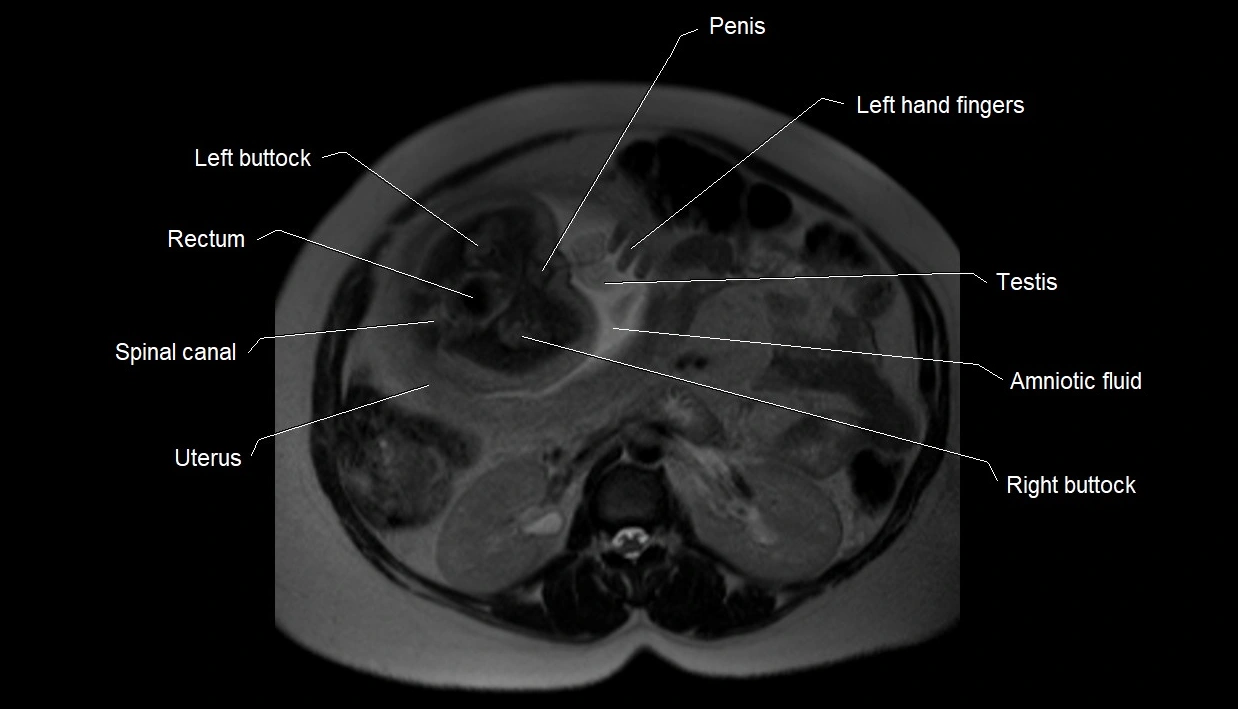

MRI Appearance

T2 HASTE (T2 GRE):

• Amniotic fluid shows very bright hyperintense signal

• Provides natural contrast against fetus and placenta

• Small particles (vernix) may appear as scattered hypointense foci within bright fluid